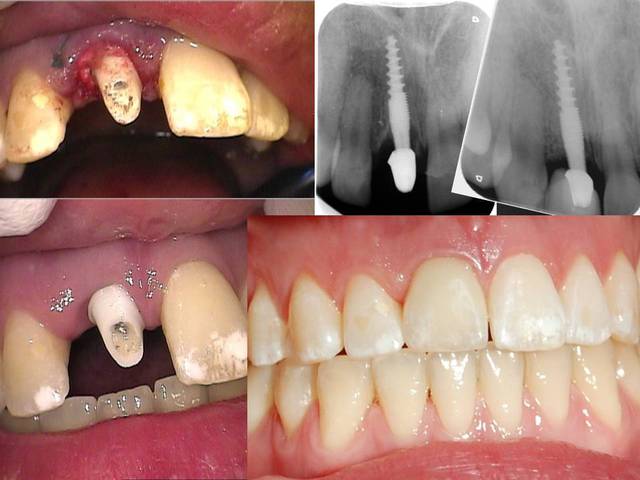

Un patient de 52 ans présente une fracture de racine au site 26.Après division de la racine, extraction de la dent,préparation de la cavité avec un foret conique triangulaire (3 faces,condensation de l´os), puis implantation à 50 Ncm (implant 10mm long, 4,5mm diamètre).Utilisation d´acide hyaluronique pour stimuler la synthèse des ostéoblastes.Pose d´un clip gingival pour préformer la gencive.Après 7 semaines, réalisation d´une empreinte fermée en 5 minutes.Une semaine après, fixation de la couronne définitive ( on observe déjà une ostéointégration).

Pour laisser entrevoir la technique MIMI (Minimale Invasive Method Implantation) développée par le Dr Armin Nedjat voilà la séquence en photos et radios d'un cas d'extraction implantation immédiate technique simplifiée.

Bonjour je connais bien les techniques du Dr Nedjat pour les pratiquer depuis de nombreuses années. Il me demande de l'aider un peu vu la barriere de la langue pour la réponse aux questions.. On voit sur une radio que passer dans le septum impose de faire un "summers modifié", du type carote osseuse condensée à l'osteotome pour preparer un lit implantaire dans ce cas on peu placer un 8mm en base large et avoir un pilier dans l'axe. OK. Ca n'a pas été son choix car il developpe en Allemagne depuis 15 ans sa technique dite MIMI (voir mon post précédent) qui consiste a fraire une osteotomie avec des expanseurs suite à un forage minimal pour obtenir une stabilité primaire tres élevée la plupart du temps 60/70N..Cette technique est tres répandue en Allemagne, plus de 3000 confreres l'utilisent avec un systeme monobloc ou deux pieces..je vais poster dans les jours qui viennent sufisament d'infos pour que vous puissiez vous faire une idée, j'ai des dizaines de cas iconographiés de A à Z. Dans ce cas oui c'est un 4,5mm, l'implant est posé avec son "shuttle" partie intermédaire porte implant laissé intra muqueux et qui "encaisse" le couple de serrage important de la pose. Dessus est clipsé un "gingiva clips" qui est un conformateur gingival laissé pour la cicatrisation. L'empreinte se fait en laissant Shuttle et gingiva clips. Le shuttle est déposé pour la mise du pilier. Il y a toute une technique ..description à venir et cas cliniques aussi ..A suivre..